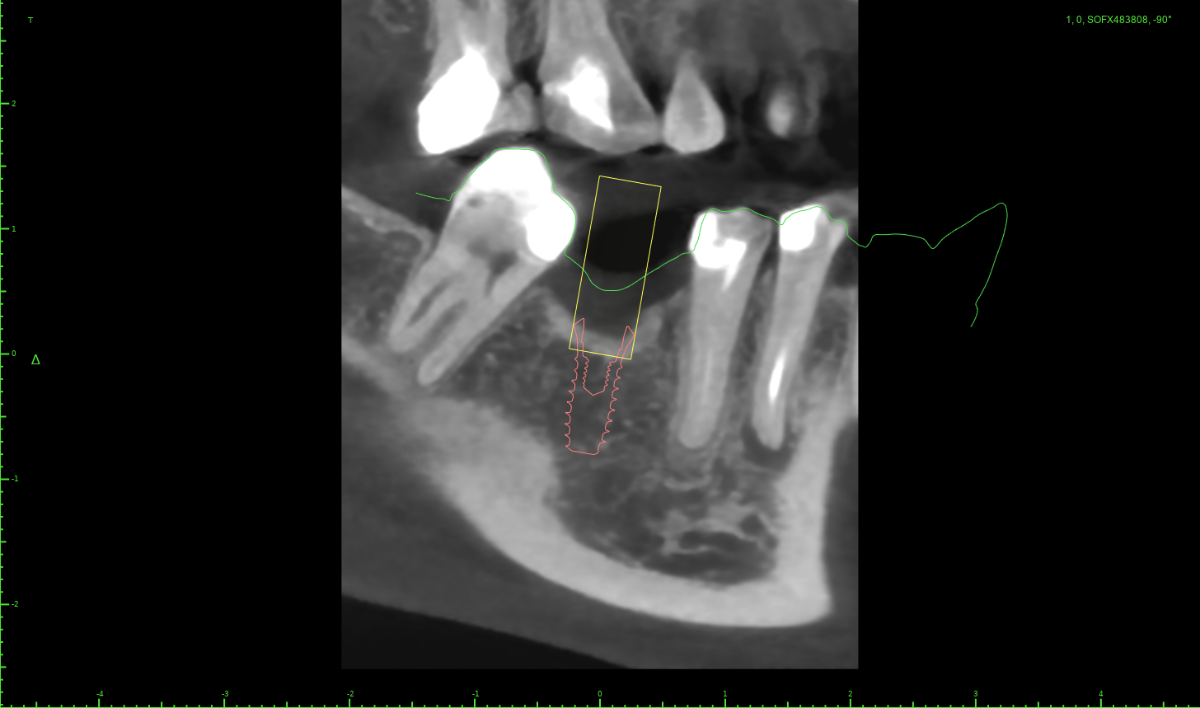

Женька Опубликовано 25 июня, 2025 Поделиться Опубликовано 25 июня, 2025 Коллеги, почему так? Сканер медит 700, скан мой-вчерашний. Кт месячной давности, пациентка зубы не лечила за это время. В области моляра чётко, в области премоляра не совпадает скан. Постоянно с таким сталкиваюсь, не понимаю в чём проблема. Ссылка на комментарий

АнтонТЛТ Опубликовано 25 июня, 2025 Поделиться Опубликовано 25 июня, 2025 Везде есть погрешность, в кт погрешность больше чем на скане 2 2 Ссылка на комментарий